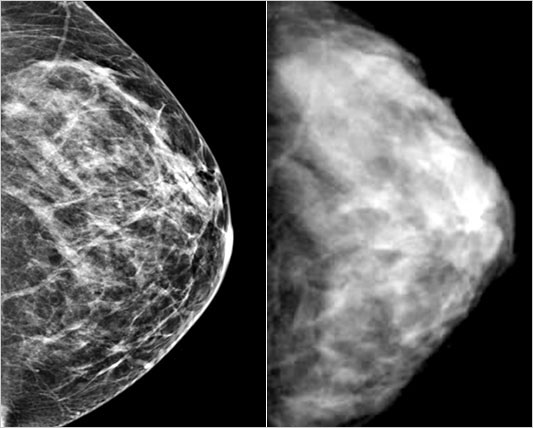

석회화는 모양을 보면 암 여부를 어느 정도 구별할 수 있습니다. 물론 모양만으로 암 여부를 명확히 구별할 수 없기 때문에 조직검사를 실시해야 합니다.

예전에는 외과적 수술로 조직검사를 했기 때문에 유방에 큰 흉터가 남게 되는 경우가 많았습니다만, 최근에는 입체정위 진공절제술을 통해 흉터를 거의 남기지 않고 석회화를 절제할 수 있습니다.